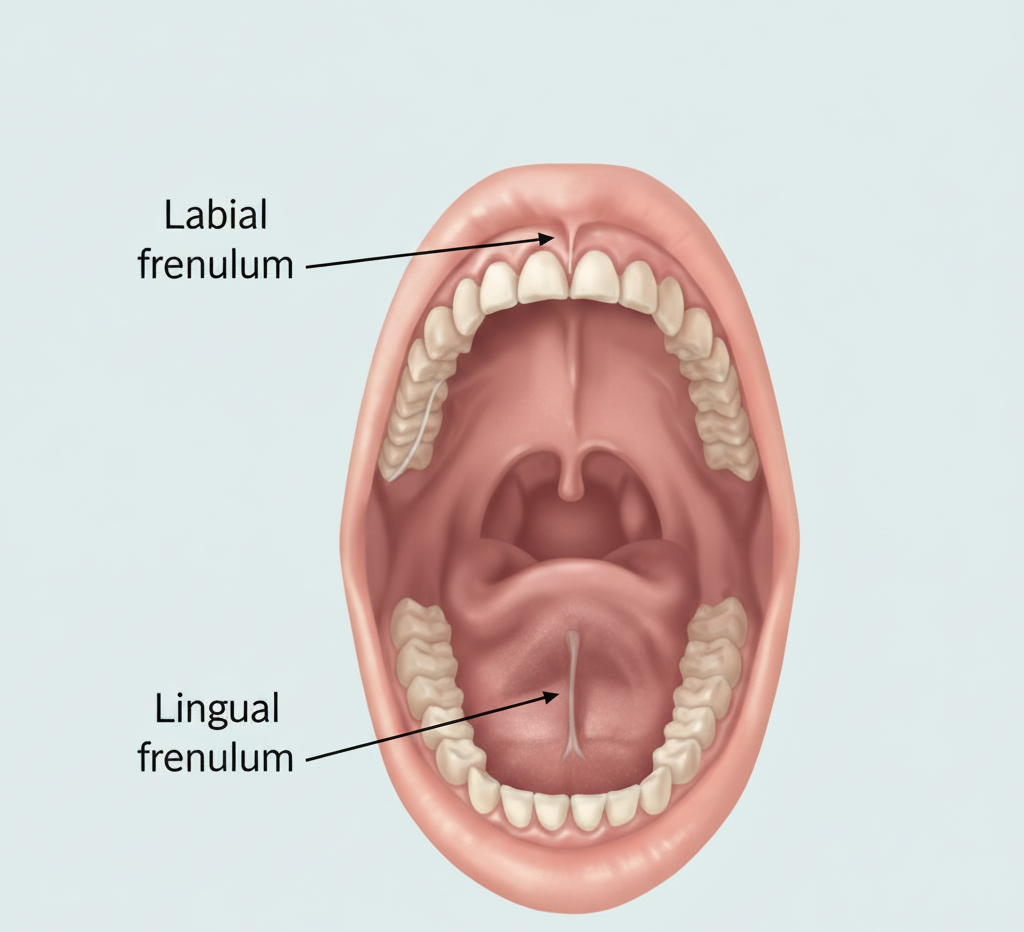

Frenectomy - Minor-Surgery In Chennai

A frenectomy is a minor surgical procedure that involves the removal or modification of a frenum—a small fold of tissue that connects or restricts movement in certain areas of the mouth. There are two main types of frena in the oral cavity: the labial frenum, which connects the upper or lower lip to the gums, and the lingual frenum, which connects the underside of the tongue to the floor of the mouth.This frenectomy minor surgery in Chennai is available at Best Dental Clinic – Dr N Deenadayalan T Nagar, Chennai and Dr Julian’s Laser Dental Clinic Tambaram, Chennai

When is a Frenectomy Needed?

-

Presence of a large gap between upper front teeth

-

Difficulty in breastfeeding due to restricted tongue movement (in infants)

-

Speech difficulties in children or adults

-

Recession of the gums due to a pulling frenum

-

Difficulty in cleaning or maintaining oral hygiene

-

Orthodontic or prosthodontic treatment preparation

Treatment

A frenectomy is a quick, outpatient procedure typically done under local anesthesia. The dentist or oral surgeon cuts or removes the problematic frenum using:

-

Scalpel (traditional method)

-

Laser (more modern and less invasive, with faster healing and minimal bleeding)

Patients can get a frenectomy minor surgery at Best Dental Clinic – Dr N Deenadayalan T Nagar, Chennai and Dr Julian’s Laser Dental Clinic Tambaram, Chennai, with expert care and modern techniques.

Tongue-Tie Removal - Minor-Surgery In Chennai

Tongue-tie removal, also known as a lingual frenectomy or frenotomy, is a minor surgical procedure performed to correct a condition called ankyloglossia—where the lingual frenum (the small band of tissue under the tongue) is too short, thick, or tight.

This restricts the tongue’s range of motion and can interfere with normal functions like breastfeeding, speaking, swallowing, and even oral hygiene. This Tongue-tie removal minor surgery in Chennai is available at Best Dental Clinic – Dr N Deenadayalan (Pondy Bazaar, T Nagar, Chennai) and Dr Julian’s Laser Dental Clinic, Chennai.